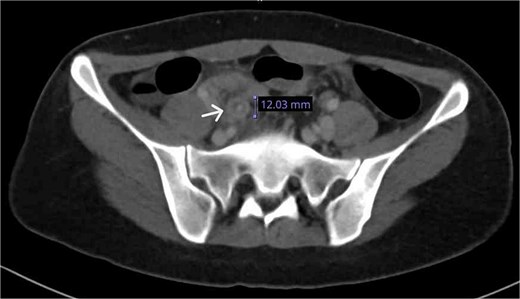

The patient underwent laparoscopic appendectomy. Intraoperatively, the appendix was inflamed with early adhesions to the anterior abdominal wall and a small volume of purulent pelvic fluid. Histopathological examination revealed transmural acute inflammation with multiple calcified Schistosoma ova in the mucosa and submucosa, confirming SA (Fig. 3).

Histopathological section stained with H&E for the excised appendix: (a) (magnification 4×) an appendix shows acute appendicitis with transmural acute inflammation, a calcified Schistosoma egg is indicated by an arrow. (b) (magnification 40×) multiple calcified Schistosoma eggs in the submucosal layer of the appendix (arrows).